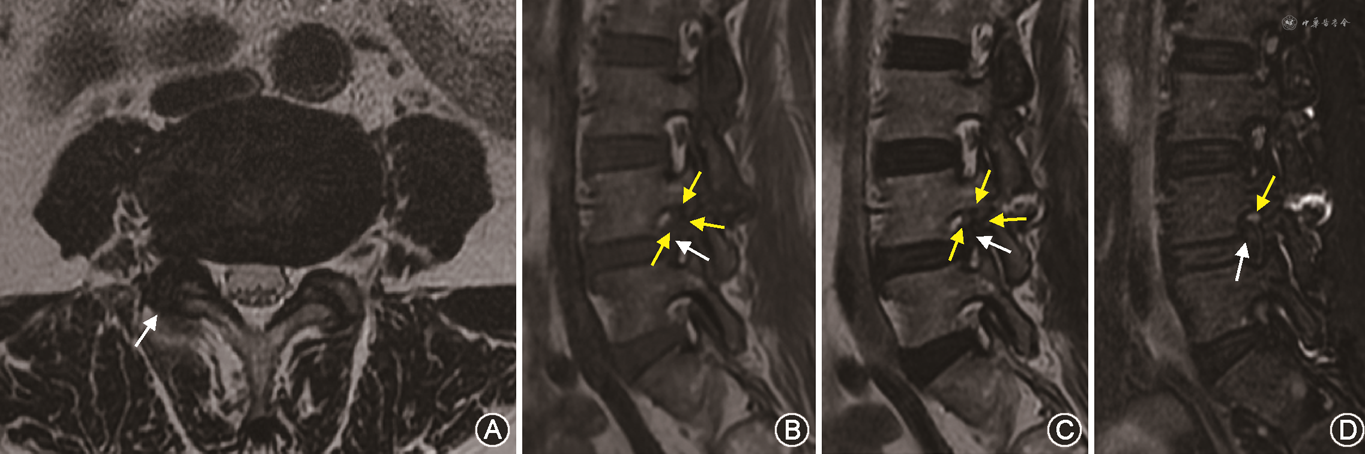

1. Lee系统:83例患者中,评估为0级的有21例,其中保守组17例,手术组4例,MRI表现为椎间孔无狭窄,椎间孔内神经根周围无脂肪闭塞(图2);评估为1级的有31例,其中保守组22例,手术组9例,MRI表现为椎间孔轻度狭窄,椎间孔内神经根周围脂肪有两个相对方向的闭塞,未看到神经根的形态学变化(图2, 3, 4);评估为2级的有11例,其中保守组3例,手术组8例,MRI表现为椎间孔中度狭窄,椎间孔内神经根周围脂肪有4个方向的闭塞,神经根无形态学变化(图3);评估为3级的有20例,其中保守组7例,手术组13例,MRI表现为椎间孔严重狭窄,出现神经根塌陷或形态学改变,部分显示欠清晰(表1)。

2. 改良系统:83例患者中,评估为0级的有3例,其中保守组3例,手术组无病例,MRI表现为椎间孔无狭窄,神经根周围无脂肪闭塞;评估为1级的有19例,其中保守组18例,手术组1例,MRI表现为椎间孔轻度狭窄,神经根无明显形态学改变,神经根周围脂肪闭塞小于神经根周长的50 %(图2);评估为2级者14例,其中保守组13例,手术组1例,MRI表现为椎间孔中度狭窄,神经根无明显形态学改变,神经根周围脂肪闭塞大于神经根周长的50 %;评估为3级者47例,其中保守组15例,手术组32例,MRI表现为椎间孔重度狭窄,清晰显示神经根被挤压在椎间孔上壁并明显变细或塌陷(图3、4,表1)。

多项研究认为T1WI序列神经根周围脂肪闭塞程度是对IFS程度最具提示意义的指征[5, 6, 7, 8],应用最广泛的是Lee系统[7, 8, 9, 10]。本研究发现,Lee系统对常为偏心性狭窄的FLDH-IFS分级有很大的缺陷,如对神经根周围有1个方向脂肪闭塞者(0~1级之间者)不能准确地分级,既可以评估为0级也可以评估为1级,同样对神经根周围有3个方向脂肪闭塞者(1~2级之间者)也不能准确地分级,既可以评估为1级也可以评估为2级,导致评估者很难做出一致准确的判断,可重复性低。本研究结果显示两种系统评级结果之间差异具有统计学意义,改良系统优于Lee系统,改良系统的观察一致性也明显高于Lee系统。Lee系统的0~3级之间部分(0~1级之间、1级、1~2级之间、2级)由改良系统合理有效地衔接、整合为2个级别(神经根周围脂肪闭塞小于神经根周长50 %的1级和大于50 %的2级),能够全面、准确地分级。并且在Lee分级系统中,神经根受压情况常不能清晰显示,而改良系统增加了T2WI-FS序列,能够清晰、准确地显示高信号神经根的位置(如神经根被挤压在椎间孔上壁)、大小(如明显变细)、形态(如形态学改变、塌陷),从而能够准确地分级。改良系统对这些影像学表现特点的评估,明显优于Lee系统。

T2WI-FS序列显示神经根受压程度最清晰,所以快速而准确的评估方法是先看T2WI-FS序列。如果神经根明显被挤压在椎间孔上壁并明显变细或塌陷时就属于3级;如果神经根没有明显形态学改变时,再看T1WI、T2WI显示神经根周围脂肪闭塞的程度。若神经根周围脂肪闭塞大于神经根周长的50%时为2级,若神经根周围脂肪闭塞小于神经根周长的50 %时为1级,若神经根周围没有脂肪闭塞时为0级。改良系统特别是对较重的2、3级患者能够准确地分级,因为这个分级不是取决于椎间孔内神经根周围脂肪闭塞方向的个数,而是取决于椎间孔内神经根周围脂肪闭塞占神经根的周长比。